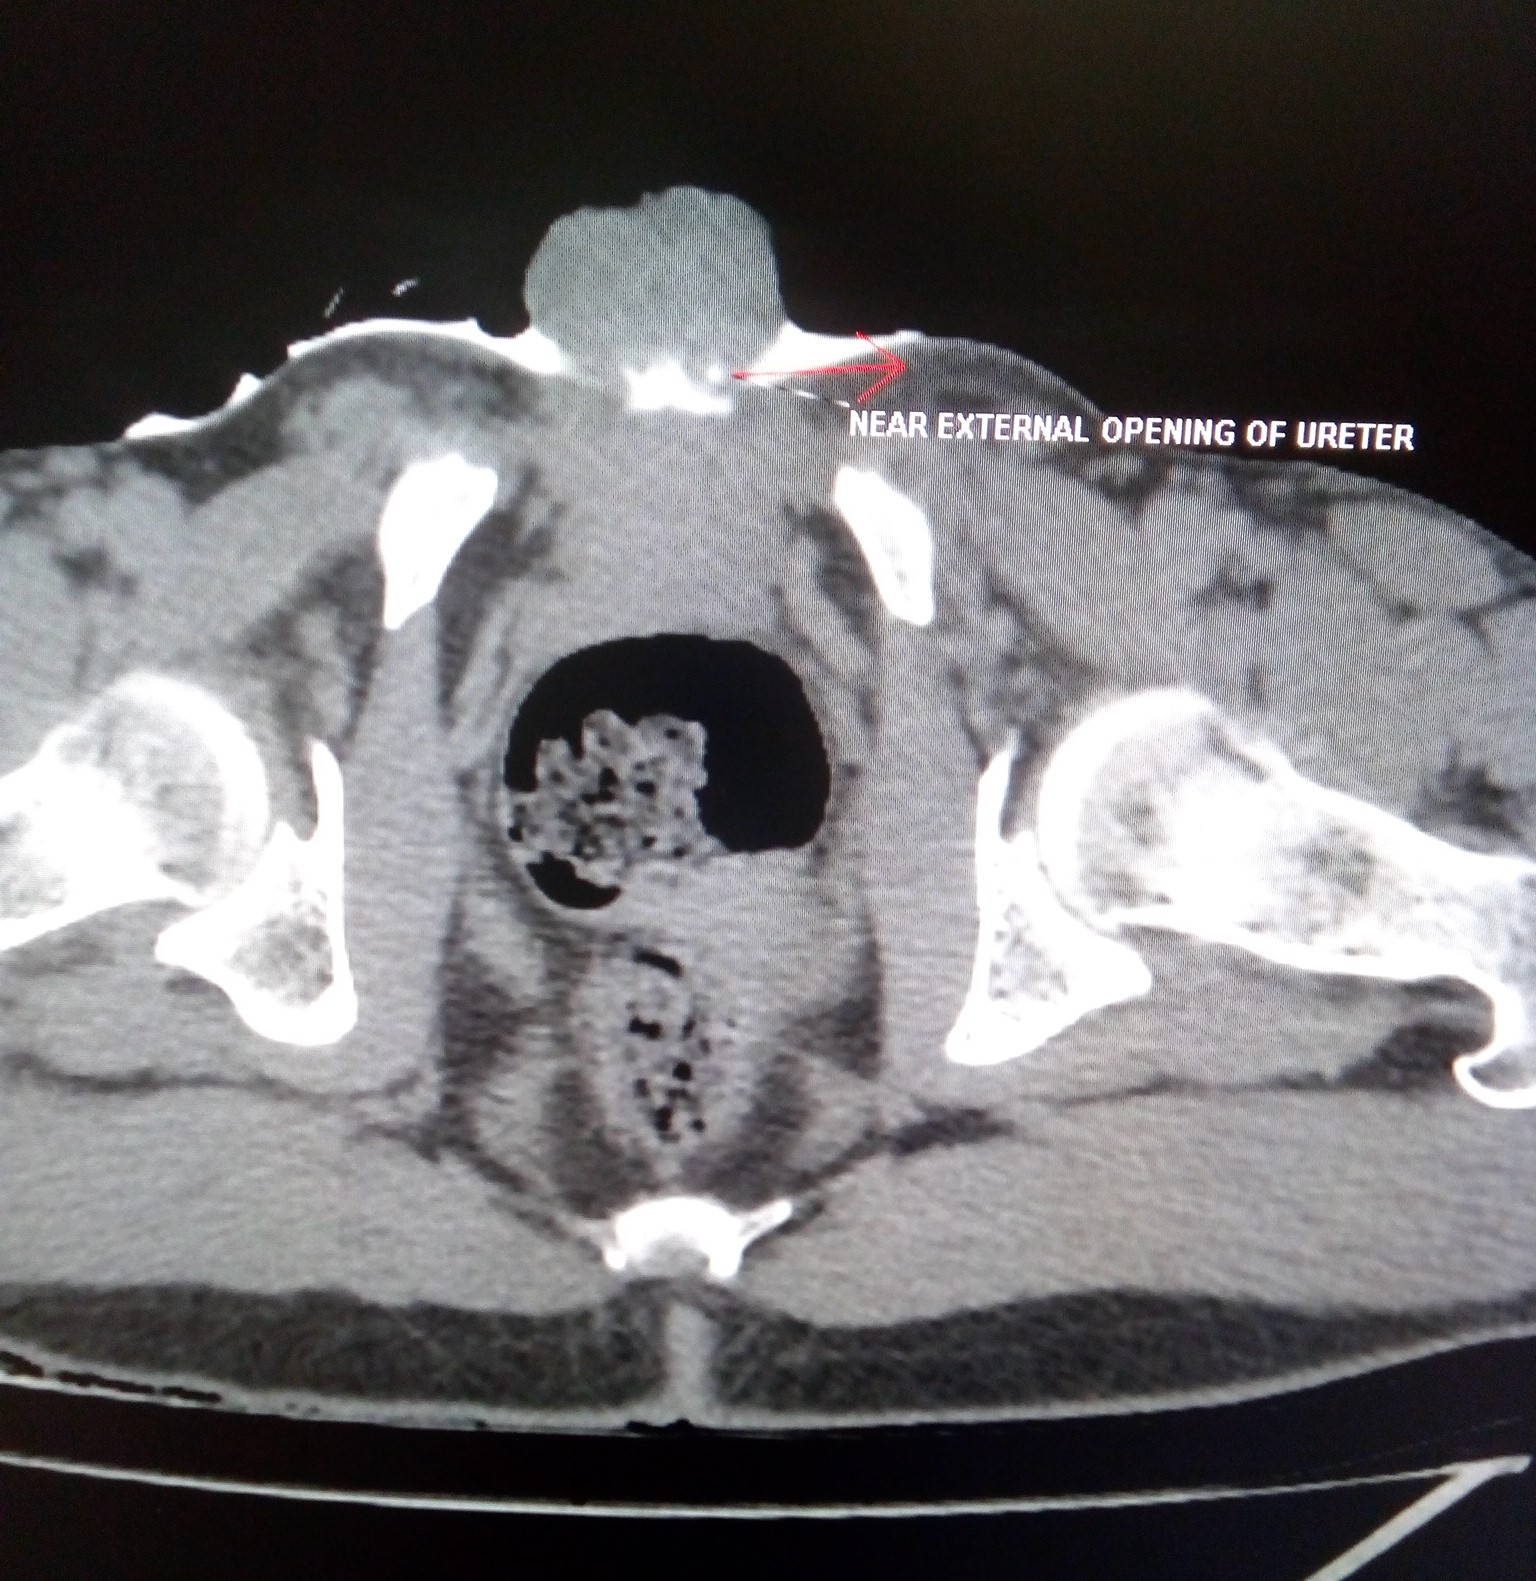

An abnormality of formation of the bladder and the bony pelvis. This image shows a neonate with bladder exstrophy and complete epispadias. Ronald rabinowitz and jimena cubillos.

Ronald rabinowitz and jimena cubillos. This image shows a neonate with bladder exstrophy and complete epispadias. The bladder does not form into its normal round shape but instead is flattened and exposed on the abdominal wall.

Bladder Exstrophy Or Ectopia Vesicae Is Characterized By A Deficient Lower Anterior Abdominal Wall Along With The Anterior Walls Of Urinary Bladder.